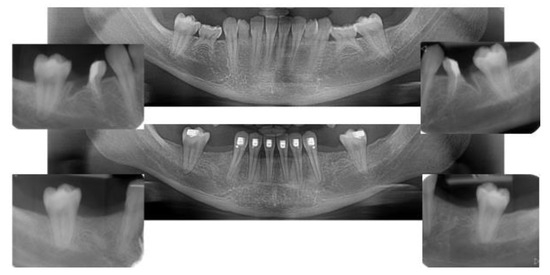

2.4.1. Radiographic Measurements

2.5. Individual Cases Description

- Case 1:

- Case 2:

- Case 3:

- Case 4:

- Case 5: